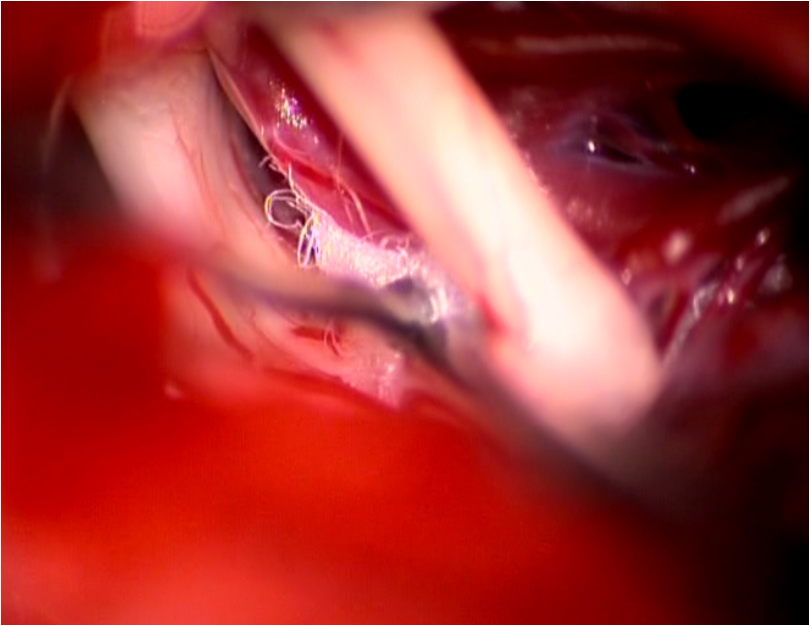

三叉神經微血管減壓手術切口

術中顯微鏡鏡下神經顯露